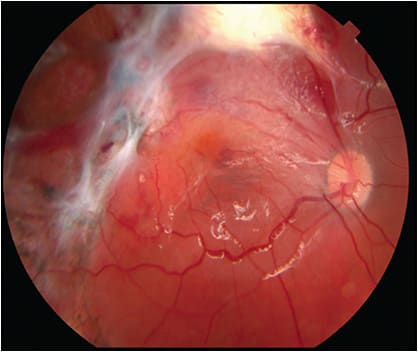

The timing of RD repair after OGR is controversial.33-37 The best time for intervention for RD repairs may be 7 days to 15 days after injury, because this creates an opportunity for the open globe wound to heal, for inflammation to subside, and for initiation of spontaneous posterior vitreous detachment if none was present at presentation.6,23,38 Proliferative vitreoretinopathy may begin to develop and progressively increase within 2 weeks to 6 weeks of injury in presence of retinal tears and RD (Figure 1).39 Corneal edema can be severe enough to preclude a view of the posterior pole that would allow retinal surgery. Vitreoretinal surgery sometimes can be delayed until the corneal edema improves. If retinal surgery is deemed urgent or emergent and if the view of the posterior pole is inadequate due to corneal laceration or edema, one may combine penetrating keratoplasty and PPV using a temporary keratoprosthesis intraoperatively.40-42 Severely injured deformed globes with poor anterior segment anatomy may not be candidates for this procedure.43 Endoscopic vitrectomy may be an option in some eyes with anterior-segment media opacities and an inadequate view of the posterior segment. Endoscopic vitrectomy surgery is performed using image projection from the camera in the probe onto a 2-dimensional nonstereopsis monitor. Identification of the exact location of the endoscope probe requires the recognition of normal landmarks within the eye. The ocular structures may be displaced from their normal location in severely injured eyes, and extensive pathology can render this technique challenging.1,43